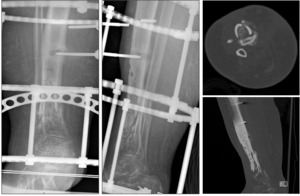

By eighty-seven weeks, one year after the most recent surgery, the patient is ambulating pain free in his regular work boots without assistive devices, has fully returned to work as a physical laborer, and reports he is completely back to his normal life. Most recent radiographic images demonstrate a stable tibial construct with healing of the ¾ cortices surrounding an intact cement spacer (Figure 9).

The patient’s specific case highlights the use of an antibiotic cement spacer in combination with a tibial nail to augment fixation of a tibial plafond fracture nonunion. The unique aspect of this case, however, is the retention of the cement spacer as definitive treatment without planned removal of the cement and bone grafting the void. We believe both the tibial nail and the cement both provide structural and weight bearing stability with minimal evidence of radiographic or clinical change at one year postoperatively. Four weeks after the procedure, the patient was able to bear full weight on the extremity in a boot, and returned to work with no restrictions by twenty-three weeks. He has returned to all normal activities, ambulating pain free, without ever having to have undergone the second stage procedure. At this time, his imaging demonstrated bony bridging of ¾ cortices, which aligns with many publications that use bridging of 50% or 2 cortices as the standard for healed 32-34. This case, combined with the studies presented above, suggest that as a variation of cement augmentation or the Masquelet technique, a tibial nail could be inserted with the cement spacer in the first stage as an appropriate definitive fixation, and the second stage could be postponed indefinitely or performed years later if deemed necessary.